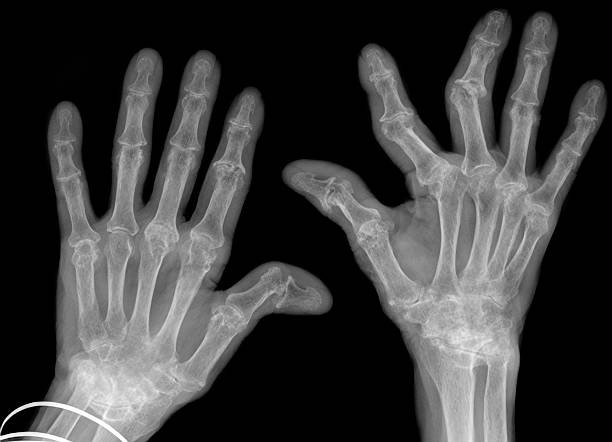

류마티스 관절염 초기증상 세 번째는 관절 통증입니다 류마티스 관절염으로 인한 관절통은 운동과 휴식과 무관하지만 손가락과 손목 통증은 류마티스 관절염에서 흔하게 나타나나 통증은 발목, 무릎, 엉덩이, 어깨, 팔꿈치와 같은 관절과 손목, 팔꿈치와 같은 좌우 관절에서도 발생합니다.

10. 류마티스 관절염 초기증상 - 뻣뻣한 손과 발

류마티스 관절염 초기증상 열 번째는 뻣뻣한 손과 발입니다. 류마티스 관절염의 초기 단계에서는 후관절에서 증상이 나타난다. 해당 증상은 손가락과 손이 만나는 관절이나 발가락과 발 사이의 관절에서 시작되며 시간이 지남에 따라 이 뻣뻣함이 다른 관절로 옮겨갈 수 있습니다. 증상은 아침이 아닌 하루 중 언제든지 나타날 수 있습니다.